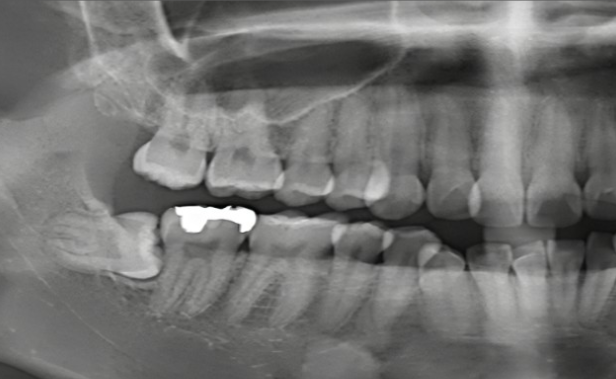

둘째, 위의 사진처럼 사랑니가 누워있는 경우

사랑니가 누워서 나있는 경우 사랑니가 구강내에 올라올 자리가 없으므로 치관만 비스듬이 솟아오른 경우로 이 경우 대부분 음식물이 잇사이에 축적되어 염증이 생기기 쉽죠.

앞치아의 충치도 같이 유발되기 쉬우므로 반드시 발치해야 하는데 일반적으로 발치는 어렵고 신논현역 사랑니 발치 구강외과 전문의와 상의하는 것이 좋습니다.